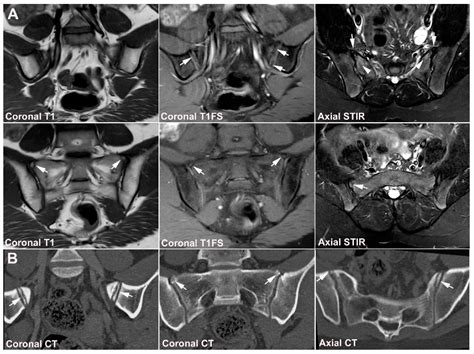

Diagnosing SI joint dysfunction involves a thorough medical history, physical examination, and sometimes imaging tests. A healthcare professional may use various diagnostic techniques to assess the SI joint, including:

• Imaging studies, such as X-rays, MRI, or CT scans, to visualize the joint and surrounding structures

In some cases, an Xray Si Joint may be recommended to confirm the diagnosis and rule out other potential causes of pain. This imaging technique provides detailed images of the joint and can help identify any abnormalities or degenerative changes.